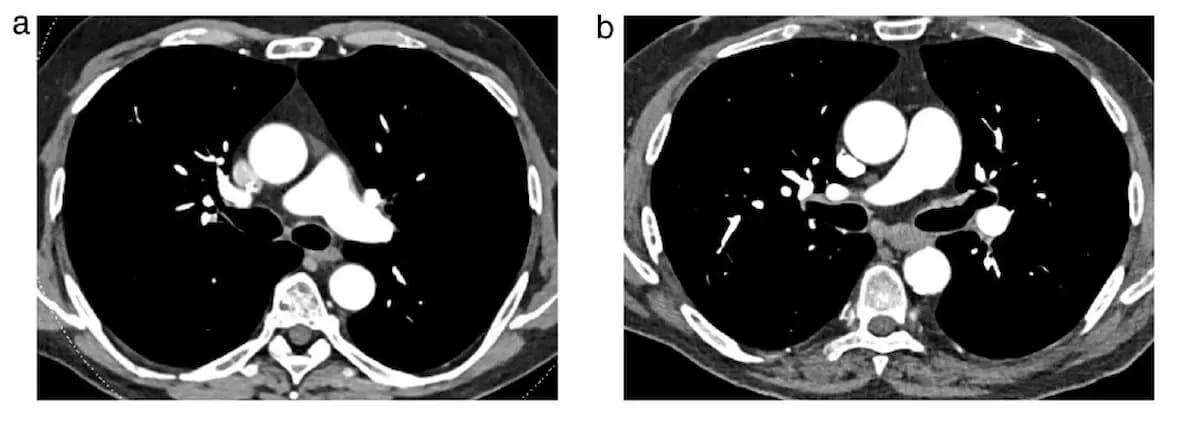

1. Citing a comparative study with PCD-CT and EID-CT in diagnosing acute pulmonary embolism (PE), the review authors noted no significant difference in mean attenuation within pulmonary arteries. They also pointed out a 61.4 percent reduction in artifacts with PCD-CT in contrast to dual-energy EID-CT and an overall 48 percent reduction in radiation dosing.

3. For CT pulmonary angiography, the use of PCD-CT in ultra-low dosing protocols offered comparable or superior image quality in comparison to standard radiation dosing with EID-CTPA, according to the review authors.